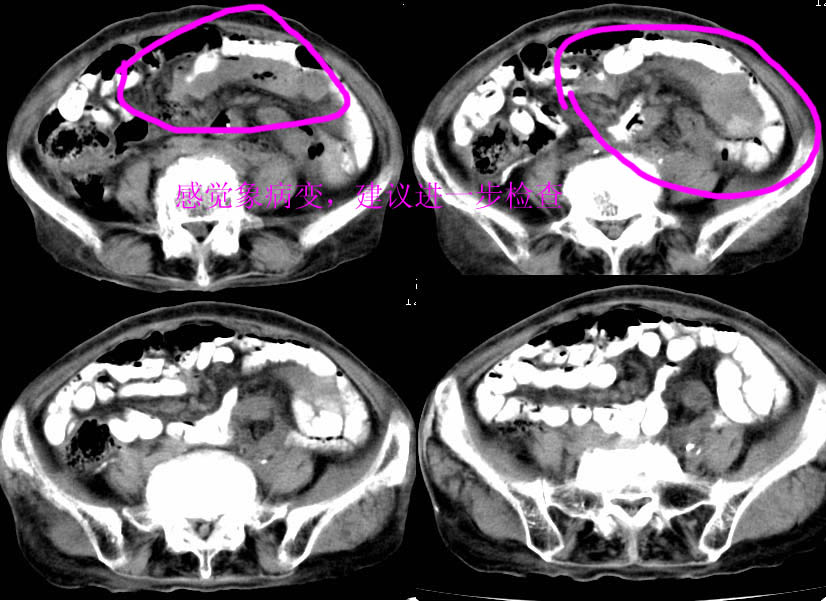

以下是引用zjzjr在2007-9-11 15:27:00的发言:[br]左侧小肠袢软组织影,其内有气体,新生物?建议胃肠造影。

以下是引用nanjing在2007-9-11 16:11:00的发言:[br]以下是引用zjzjr在2007-9-11 15:27:00的发言:[br]左侧小肠袢软组织影,其内有气体,新生物?建议胃肠造影。